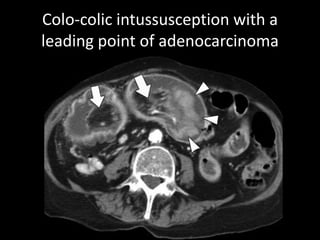

Colo-colic intussusception with a

leading point of adenocarcinoma

Colo-colic intussusception witha leading point of adenocarcinoma